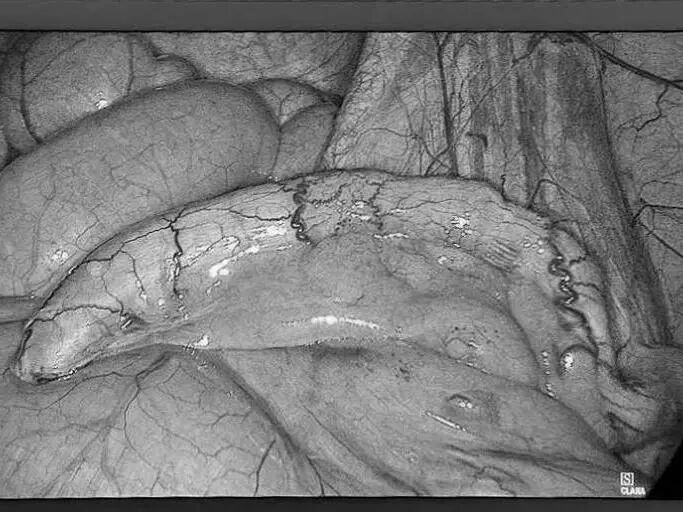

直肠脱垂是指直肠壁的一部分或全层向下移位,最终可能脱出肛门外的疾病。它并非肿瘤,但在老年人、多次分娩的女性、长期便秘或慢性咳嗽等腹压增高人群中较为常见。 【关键诱因与表现】 直肠脱垂主要因盆底肌肉、韧带等支撑结构松弛,加之长期腹压增高(如用力排便、慢性咳嗽、排尿困难)诱发。患者常感肛门坠胀或异物感,典型表现为排便或久站后有柔软肿物自肛门脱出,初期或可自行缩回,后期常需手法复位,并可伴排便困难、不尽感、肛门黏液或血性分泌物、潮湿瘙痒,严重者可能出现排便控制困难。 【治疗选择因人而异】 保守治疗(轻度或早期): 核心是消除诱因: 积极改善便秘(高纤维饮食、充足饮水、必要时遵医嘱用药)、控制咳嗽、解决排尿困难。 生活方式调整: 避免久蹲、久站、负重及用力排便。 盆底肌锻炼(凯格尔运动): 坚持锻炼有助于增强盆底支撑力。 及时复位: 轻柔地将脱出部分复位,防止卡住肿胀。 手术治疗(中重度或保守无效): 当脱垂严重影响生活、难以复位、反复出血或出现排便失禁等情况时,医生会评估手术的必要性。 手术目标是修复薄弱的支撑结构,将直肠固定在正常位置。有多种手术方式(包括微创方法),医生会根据个体情况选择最合适的方案。 【重在预防与管理】 预防的关键在于减少腹压增高因素: 1.保持大便通畅,避免用力排便。 2.积极治疗慢性咳嗽、前列腺增生等导致腹压增高的疾病。 3.坚持规律进行盆底肌锻炼。 4.维持健康体重,避免长期重体力劳动。 直肠脱垂虽然带来不适,但通过及时就医、明确诊断并接受规范治疗(包括生活方式调整和必要的医疗干预),多数患者的症状可以得到有效控制,生活质量显著提升。如有相关疑虑,建议咨询肛肠专科医生。 注:部分图片来源于网络,如有侵权,请联系删除。 贵州航天医院普外科专家简介 高大勇 普外科(肛肠外科)学科带头人、名誉主任,主任医师、教授 临床擅长:对中西医结合诊治肛肠学科各种常见病、多发病及疑难杂症等具有丰富的临床经验。 原遵义市第一人民医院(遵义医科大学第三附属医院)、遵义市中医院肛肠科主任。中华中医药学会肛肠分会常委,全国中医肛肠学科名专家,中国健康促进与教育协会肛肠分会常委,中国康复医学会肛肠疾病康复专业委员会常委,中国民间中医医药研究开发协会肛肠分会副秘书长,中国医师协会中西医结合肛肠医师专业委员会常委,国家二级心理咨询师,贵州省第一批中医名医工作指导老师,遵义市名中医,遵义市肛肠学会会长,遵义市肛肠质控中心名誉主任,遵义市中西医结合学会名誉会长,遵义市健康科普专家,原贵州省中西医结合学会肛肠分会副主任委员、贵州省中医肛肠质控中心副主任、遵义市医学会医疗鉴定委员会专家、遵义市卫生系列高评委。发表论文30余篇,主编和参编医学著作5本,主持省级科研课题2项、市级科研课题2项、院级科研课题1项。 梁 跃 中共党员,普外科党支部书记、主任,主任医师 临床擅长:对普外科各类肿瘤手术具有丰富的临床经验。 毕业于遵义医学院,遵义市医学会小儿外科学分会常务委员,遵义市肛肠协会理事,遵义市医学会核医学分会(第二届)委员会委员;荣获第三期“黔医人才计划”优秀学员称号;主持市级课题1项,完成省级课题1项,在国内各类刊物上发表论文10余篇。 钱科洪 民盟盟员,普外科副主任医师 临床擅长:从事普外科临床工作30余年,对各类普外科疾病的诊治、乳腺、甲状腺、胃十二指肠、结直肠等疾病及疑难杂症具有丰富的临床经验。 毕业于遵义医学院临床医疗系,2009年前往中山大学附属第一医院微创外科进修学习,在国内各专业期刊发表论文数篇。 贵州航天医院普外科简介 基本情况 贵州航天医院普外科成立于1968年,前身属于航天部O61基地3417医院外一科,1998年3417医院、3427医院合并后更名为普外科,下设胃肠外科、肛肠外科2个亚专业科室,拥有在全市较为先进的专科设备和技术,是中国疝病专科联盟单位,贵州医科大学附属医院胃肠外科专科联盟单位。开放床位40张,配备医护人员21人。 专科特色 普外科致力于胃肠及肛肠疾病的外科临床诊治及科研,以腹腔镜微创外科技术为本,形成以快速康复治疗胃肿瘤、结直肠肿瘤、小肠肿瘤、直肠脱垂、肥胖病、急腹症、各类疝、痔、瘘等专科特色,同时注重胃肠疾病尤其是结直肠恶性肿瘤的基础研究和临床转化研究,总体诊断和治疗水平在区域同级医院居于领先水平。 开展手术:腹腔镜下胃癌根治术,腹腔镜下袖状胃切除术,腹腔镜下胃肠道间质瘤切除术,腹腔镜下结、直肠癌根治术,胃癌、结直肠癌的精准治疗,腹腔镜下小儿疝气、成人疝修补术,腹腔镜下阑尾手术,内痔的硬化注射治疗及痔疮的微创治疗:ATH、PPH、TST,直肠脱垂的各种手术治疗,难治性伤口VSD技术,鼻胃肠管、肠梗阻导管置入术,肛肠术后间歇性导尿技术,并引进了中医适宜技术,也为各种化疗患者提供输液港安装,提高患者就医体验。 腹腔镜下腹股沟疝 无张力修补术 腹股沟疝里金斯坦(Lichtenstein)手术 PPH微创术治疗环状混合痔 黏连性或炎性肠梗阻-肠梗阻导管 腹腔镜袖状胃切除 腹腔镜阑尾切除术 腹腔镜阑尾肿瘤切除术 腹腔镜下结肠癌根治术 诊疗范围 胃肿瘤、结直肠肿瘤、小肠肿瘤、肥胖症、各类急腹症、腹部外伤、腹壁疝、便秘、直肠脱垂、痔疮、肛瘘、肛裂等胃肠、肛肠外科疾病。 END